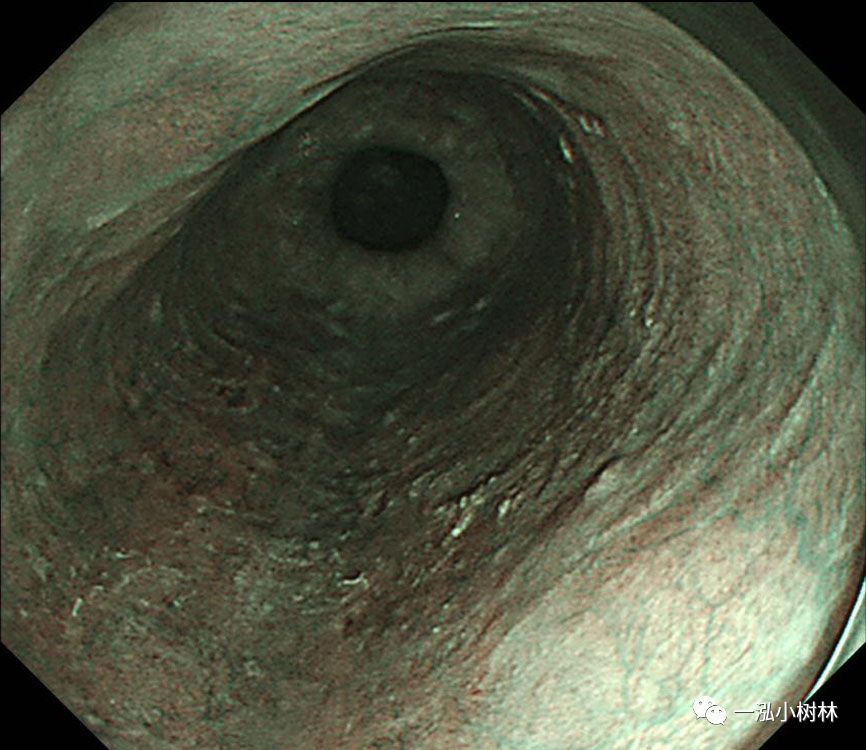

图1 白光内镜:食管中段后壁可见50mmIIb病变。